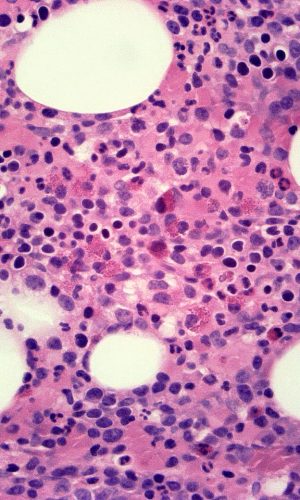

Hematopathology

Dr. Dennis Hwang is a board-certified hematopathologist and completed his hematopathology fellowship at UCSF. Contra Costa Pathology Associates offer specialized expertise in the diagnosis of various hematologic disorders including:

• Leukemias

• Lymphomas

• Myeloproliferative neoplasms

• Myelodysplastic syndromes

• Cytopenias